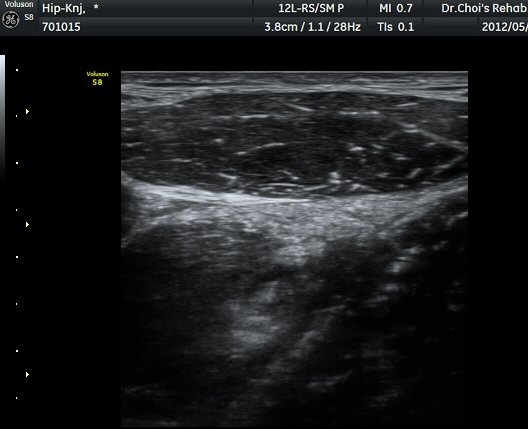

ÀüÇÏÀå°ñ±Ø(AIIS) Ⱦ´Ü¸é °Ë»ç»ó ÀüÇÏÀå°ñ±Ø°ú µÇÅðÁ÷±ÙÀÇ ÈûÁÙÀÌ °üÂûµÈ´Ù(±×¸² 1).